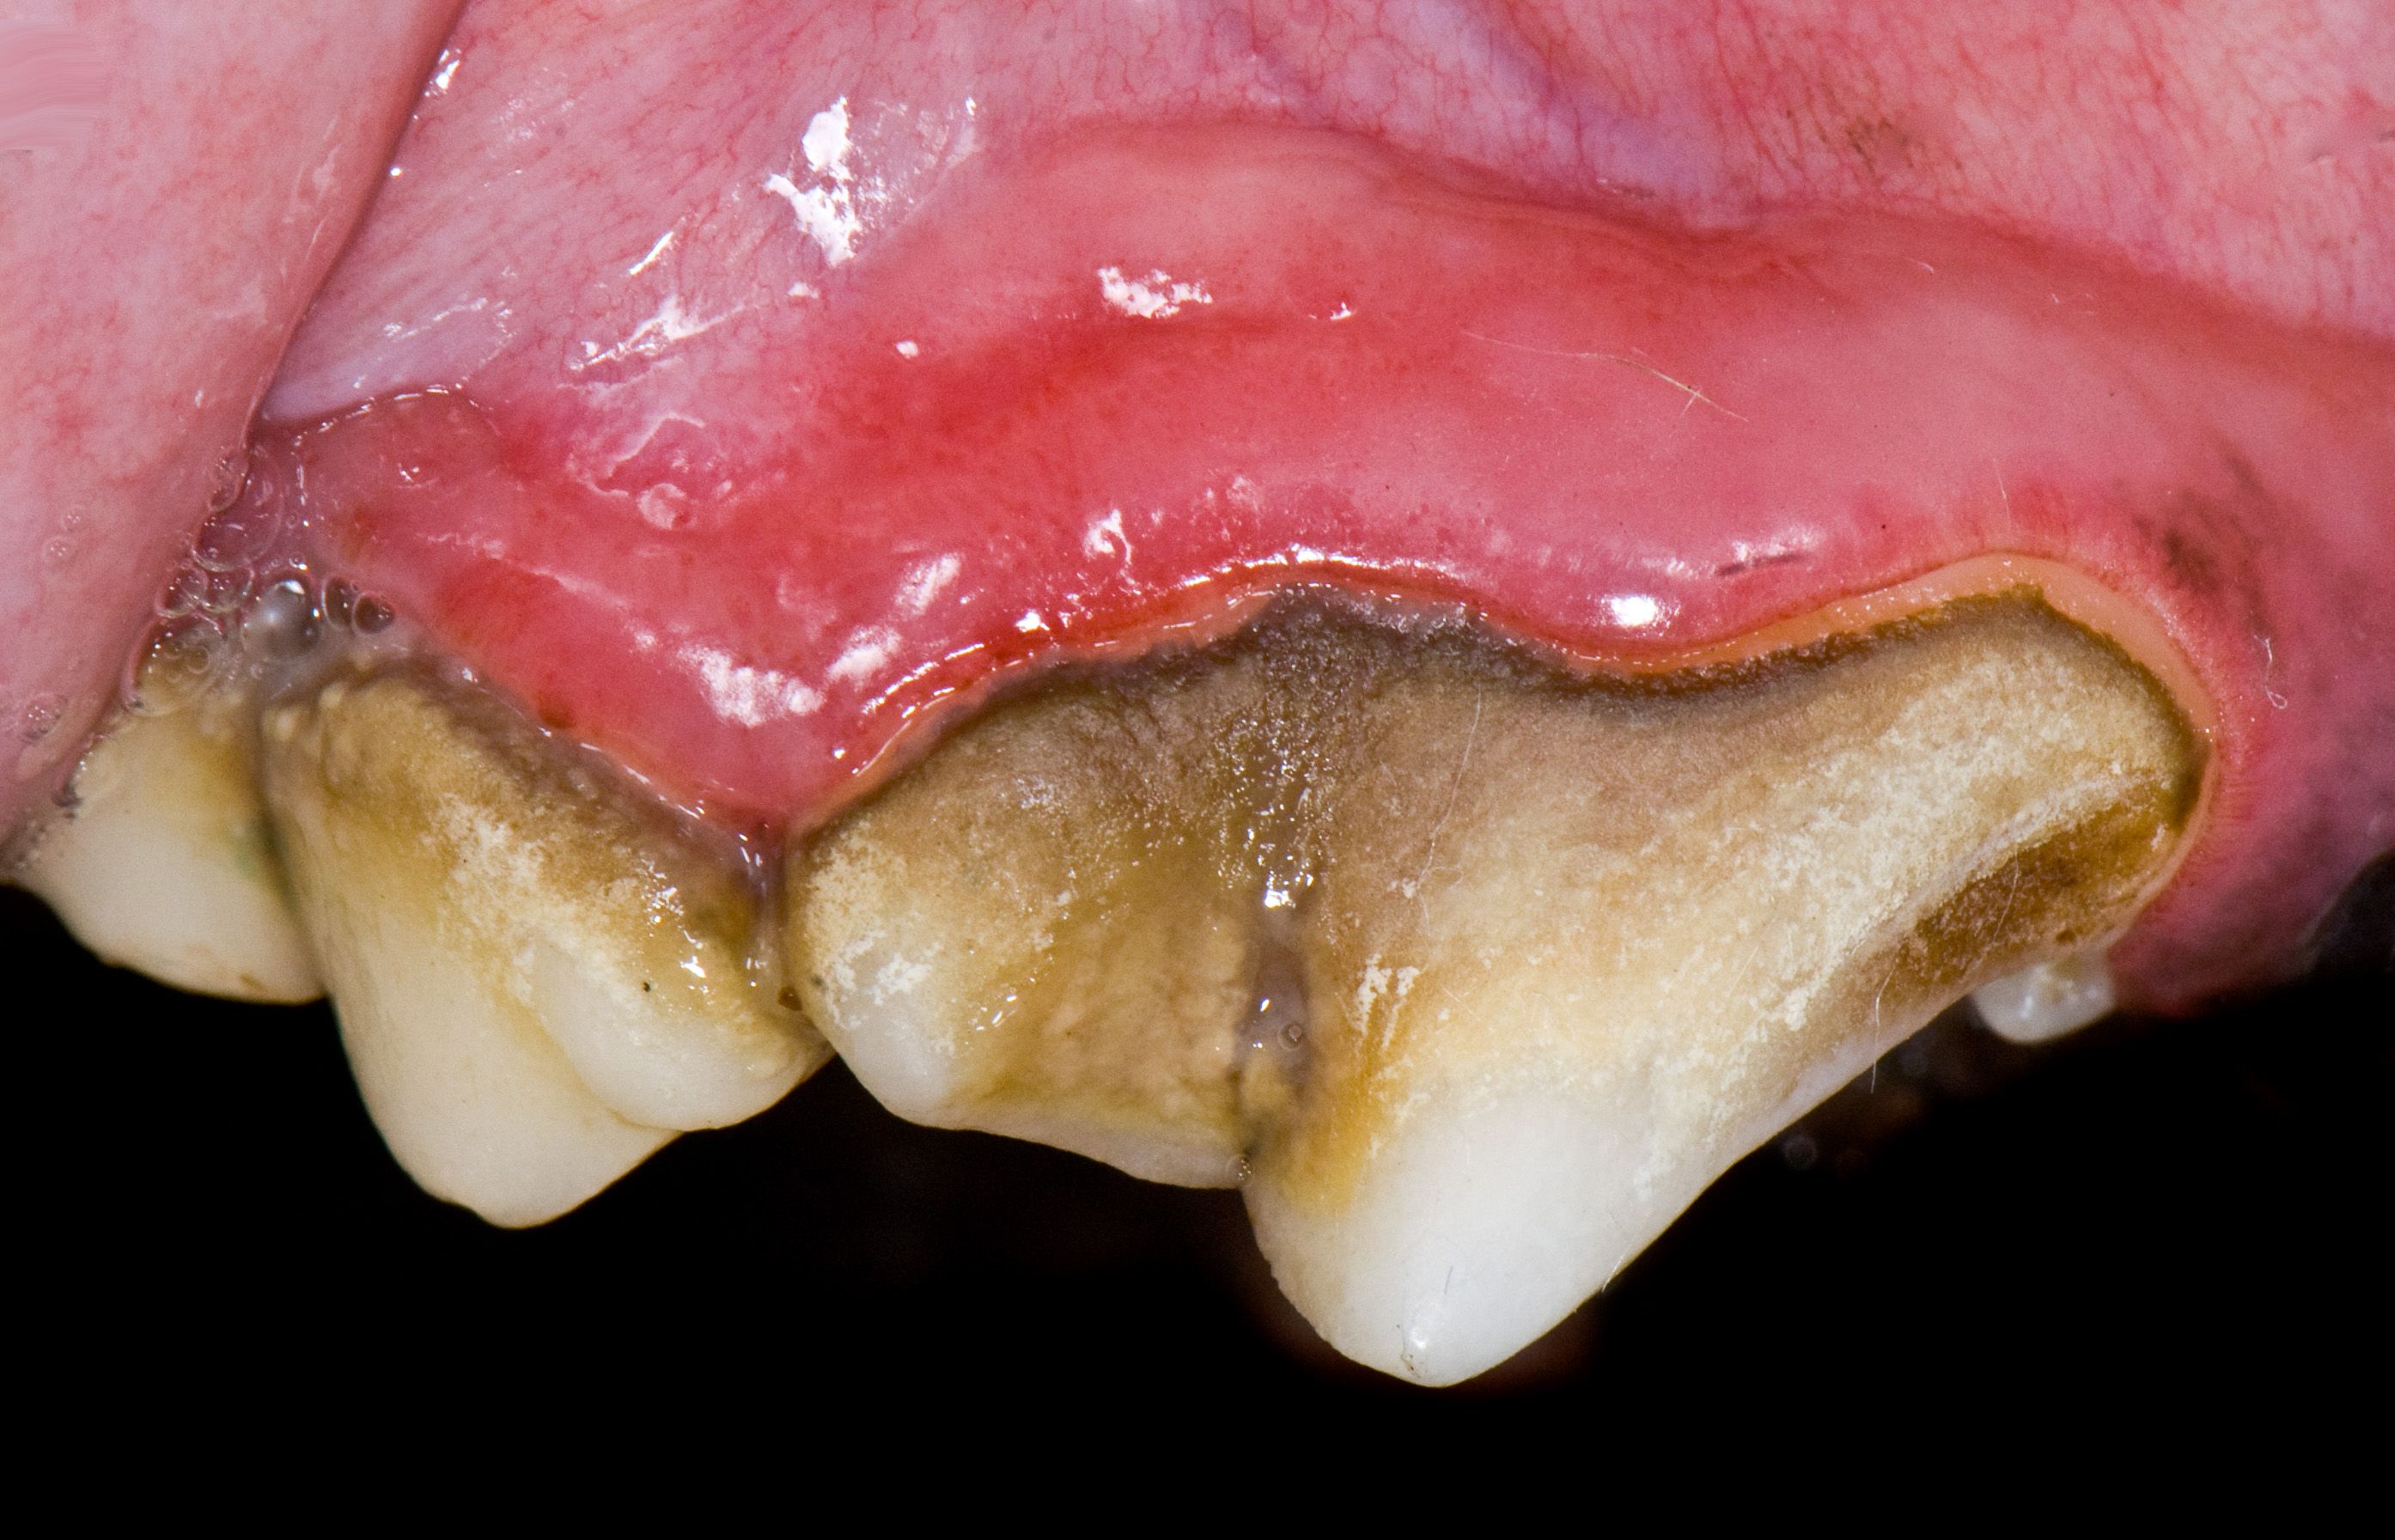

Early periodontal disease in dog.